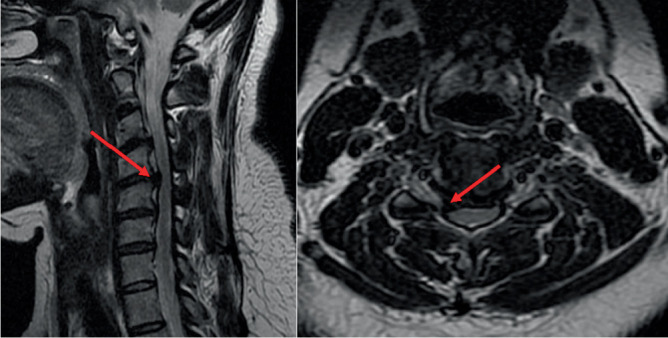

Introduction: Postoperative C5 paralysis is defined as new-onset and/or progressive muscle weakness with mild or no sensory disturbances occurring as a result of probable neuropraxia of the cervical root due to injury during surgery. Case Report: A 40-year-old female patient underwent endoscopic technique for treatment of cervical foraminal stenosis, level C4-C5. The procedure proceeded without incident in the intraoperative period. In the immediate postoperative period, the patient developed a motor deficit, Grade 2 muscle strength of the right deltoid muscle, and right C5 allodynia. Early and multidisciplinary treatment resulted in complete recovery of the neurological deficit and satisfactory evolution of the presented case. Discussion: Although postoperative C5 palsy is one of the most common postoperative complications after multilevel cervical decompression surgery, its exact mechanism remains poorly understood. Despite the various studies in this field and the possible causes described, there is still no absolute confirmation, so the formulation of hypotheses depends on clinical monitoring and postoperative examinations. The indicated treatment depends on the causal suspicion and pathophysiology and ranges from clinical drug therapy to physical therapies and/or rehabilitation. Conclusion: C5 paralysis after endoscopic surgery, although rare, is a potential complication. The likely pathophysiology is multifactorial: anatomic features of C5, manipulation of the root, and use of the bipolar in the foraminal region.